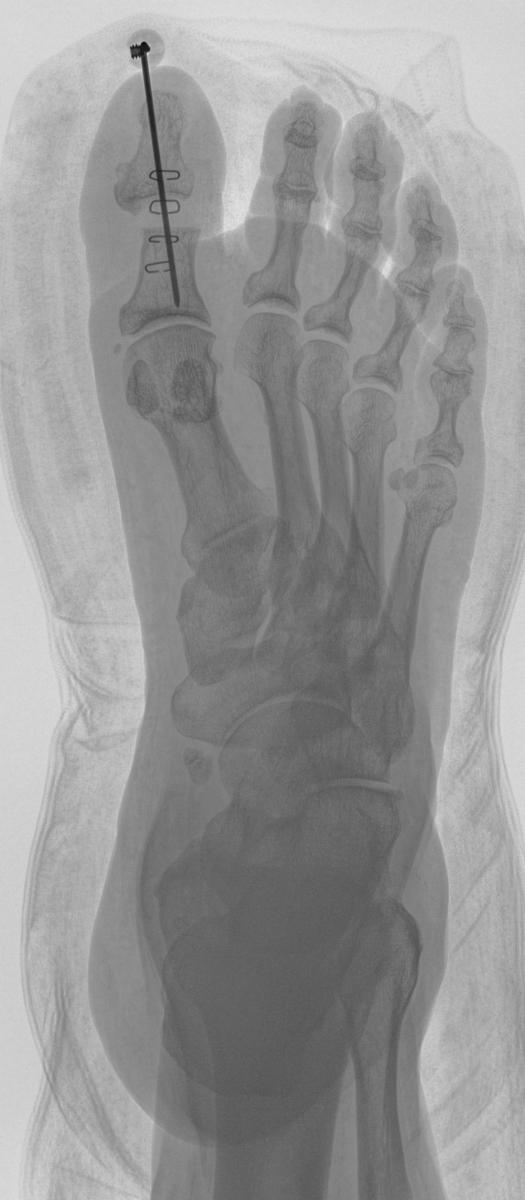

An effective treatment is a hallux interphalangeal joint arthroplasty. Perform a linear incision over the hallux interphalangeal joint. Deepen the incision to the level of the extensor tendon and transect the tendon at the joint line along with the collateral ligaments. Expose the head of the proximal phalanx and resect it with a sagittal saw. Drive a 0.062 Kirschner wire from the base of the distal phalanx out the end of the hallux and then retrograde the K-wire back through the proximal phalanx, holding the hallux in a straightened position.

Leave the K-wire in for three weeks and remove it in the clinic.2 Patients can bear partial weight on the right heel in a surgical shoe with either a cane or walker for stability. If they are unable to keep partial weight on the heel, they may just take shorter steps, placing the surgical foot forward first and bringing the unoperated foot up to meet it, rather than surpassing it, in order to avoid rolling over the toes on the operated side.